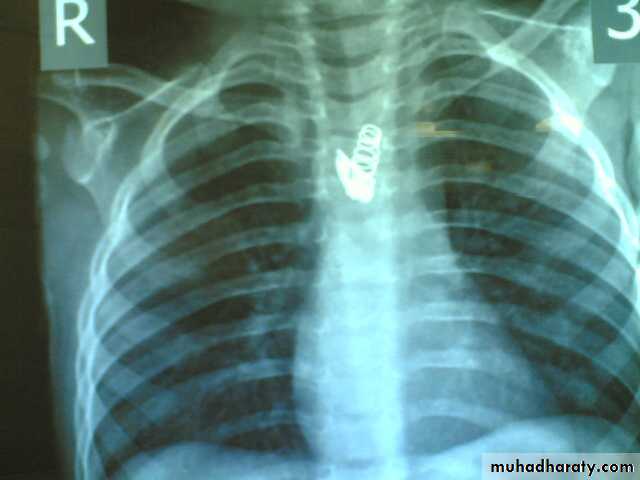

• A-Asymptomatic• Any smooth homogenous opacity of uniform density with clear cut border and little or no reaction around it on a chest X-Ray is a hydatid cyst unless proved the other wise .

• Radiological Findings

• 1-Smooth homogenous opacity (Intact H.C).• 2-Partial rupture (per vesicular pneumocyst).